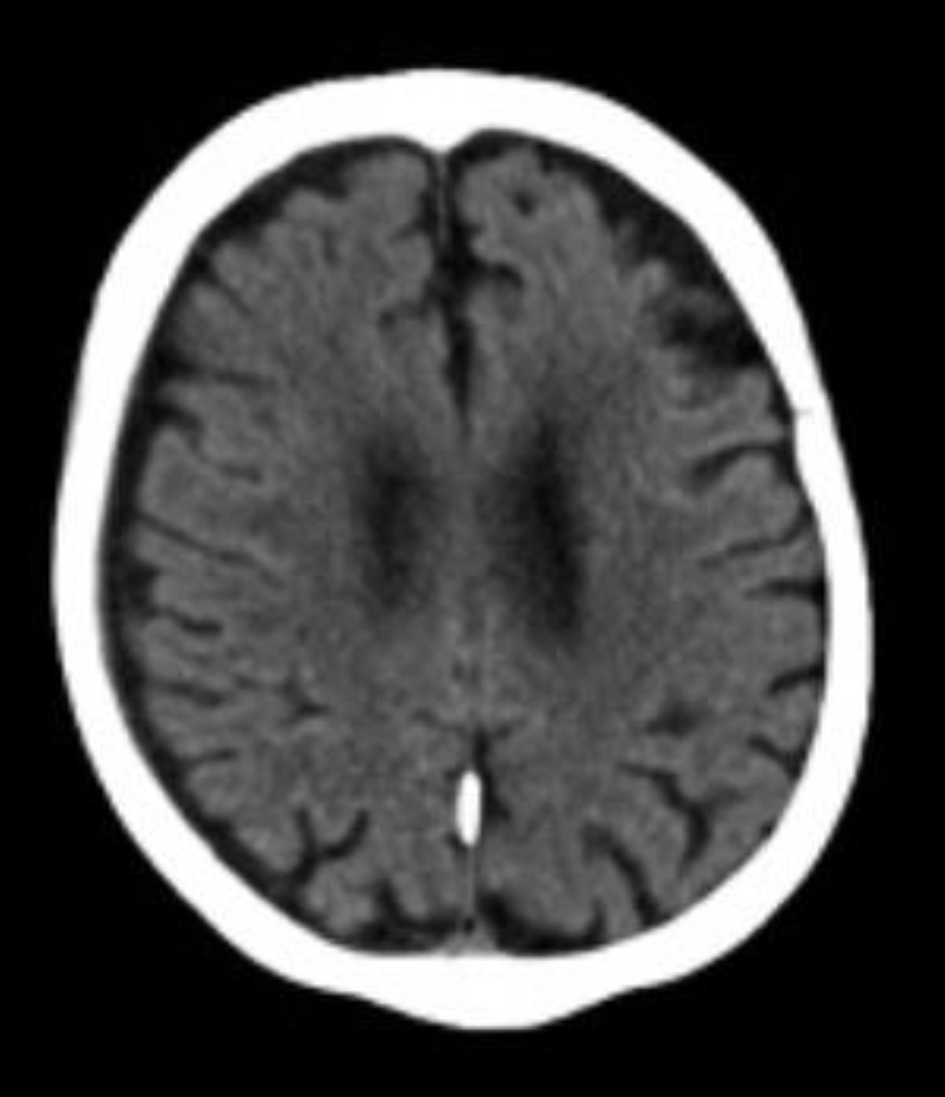

Initial computed tomography (CT) scans of the facial bones and cervical spine showed no acute abnormalities. The brain CT (Fig. 1) similarly revealed no evidence of intracranial hemorrhage, infarction, or skull fracture.

Figure 1. Non-contrast head computed tomography obtained on June 9, 2024, a few days after sustaining the fall, demonstrates no acute intracranial abnormalities.